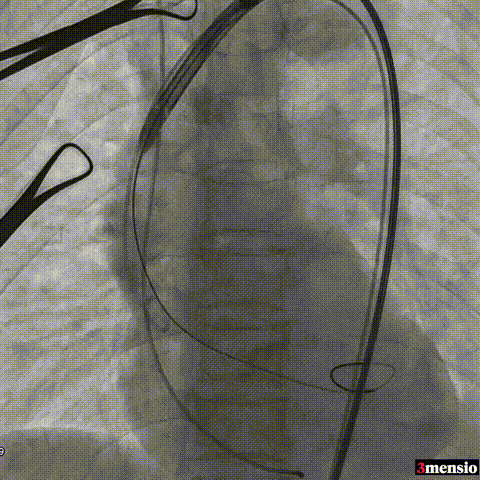

输送系统过弓

图片

瓣膜定位

瓣膜释放至工作位评估

瓣膜释放

术后即刻评估:

术后压差从66mmHg降至2mmHg,瓣膜正常工作,患者血流动力学即刻得到改善。